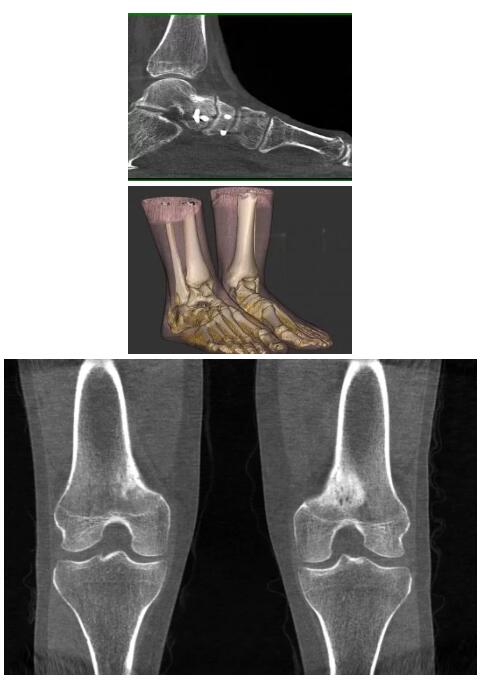

以下是這些“特立獨(dú)行”的CT所拍出來的圖像: